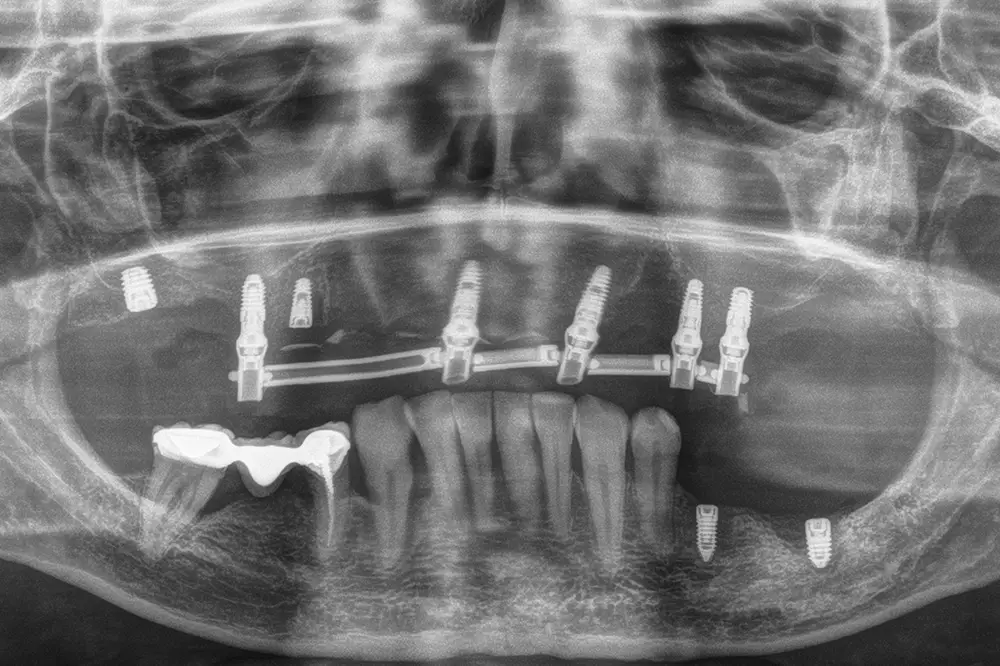

Fig. 25. Radiografía postquirúrgica tras las exodoncias y la colocación de los implantes con las diferentes técnicas comentadas anteriormente.

Transcurridos cuatro meses desde la fase inicial, ya tenemos suficiente hueso disponible en las zonas donde se realizaron las extracciones y regeneraciones con PRGF-Endoret, por lo que podemos planificar la colocación de implantes en estas áreas en un segundo tiempo quirúrgico. En el primer cuadrante, en los cortes del cone-beam realizado en este momento podemos observar una regeneración completa del alveolo tanto del molar como del premolar extraídos en la primera fase y cómo podemos colocar implantes, cortos y estrechos también en estas localizaciones (figs. 27-28). En esta fase, se aprovecha además para extraer los dos caninos que han cumplido con su función de permanecer durante la fase inicial de provisionales y cargar ya los implantes superiores de la primera fase con una prótesis atornillada mediante transepitelial múltiple y una estructura de barras articuladas, que permitirá de forma sencilla posteriormente ir añadiendo aquellos implantes que quieran cargarse seguidamente sin necesidad de repetir la estructura completa (figs. 29-31).

Figs. 29-30. Imágenes de la prótesis de carga progresiva, ya apoyada sobre los implantes superiores.

Fig. 31. Imagen de la carga de los implantes superiores de la primera fase y los dos colocados en esta segunda fase que se dejarán en dos tiempos. En este punto se lleva a cabo también la exodoncia de los caninos.